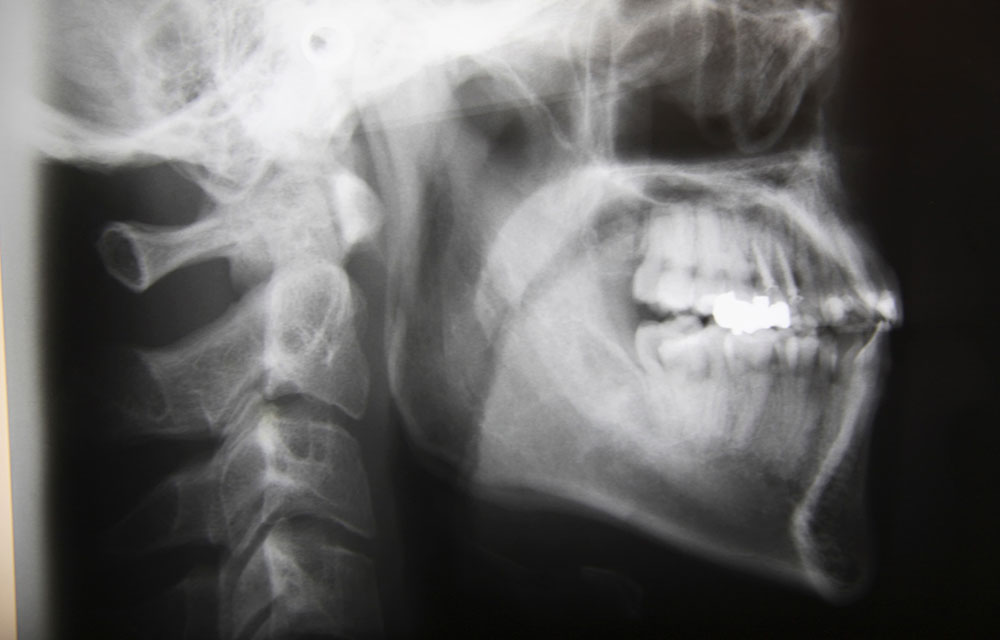

セファログラムによる分析

矯正治療を行う際には歯だけではなく、顔全体の骨格を分析するためにセファログラムというレントゲン写真を撮影します。そこから導き出される数値を元に分析し矯正治療の治療計画を立てます。分析結果によって治療の際に抜歯の有無も判断します。

また、レントゲン写真だけでなく、模型から計算して導き出される数値も重要な判断基準となります。